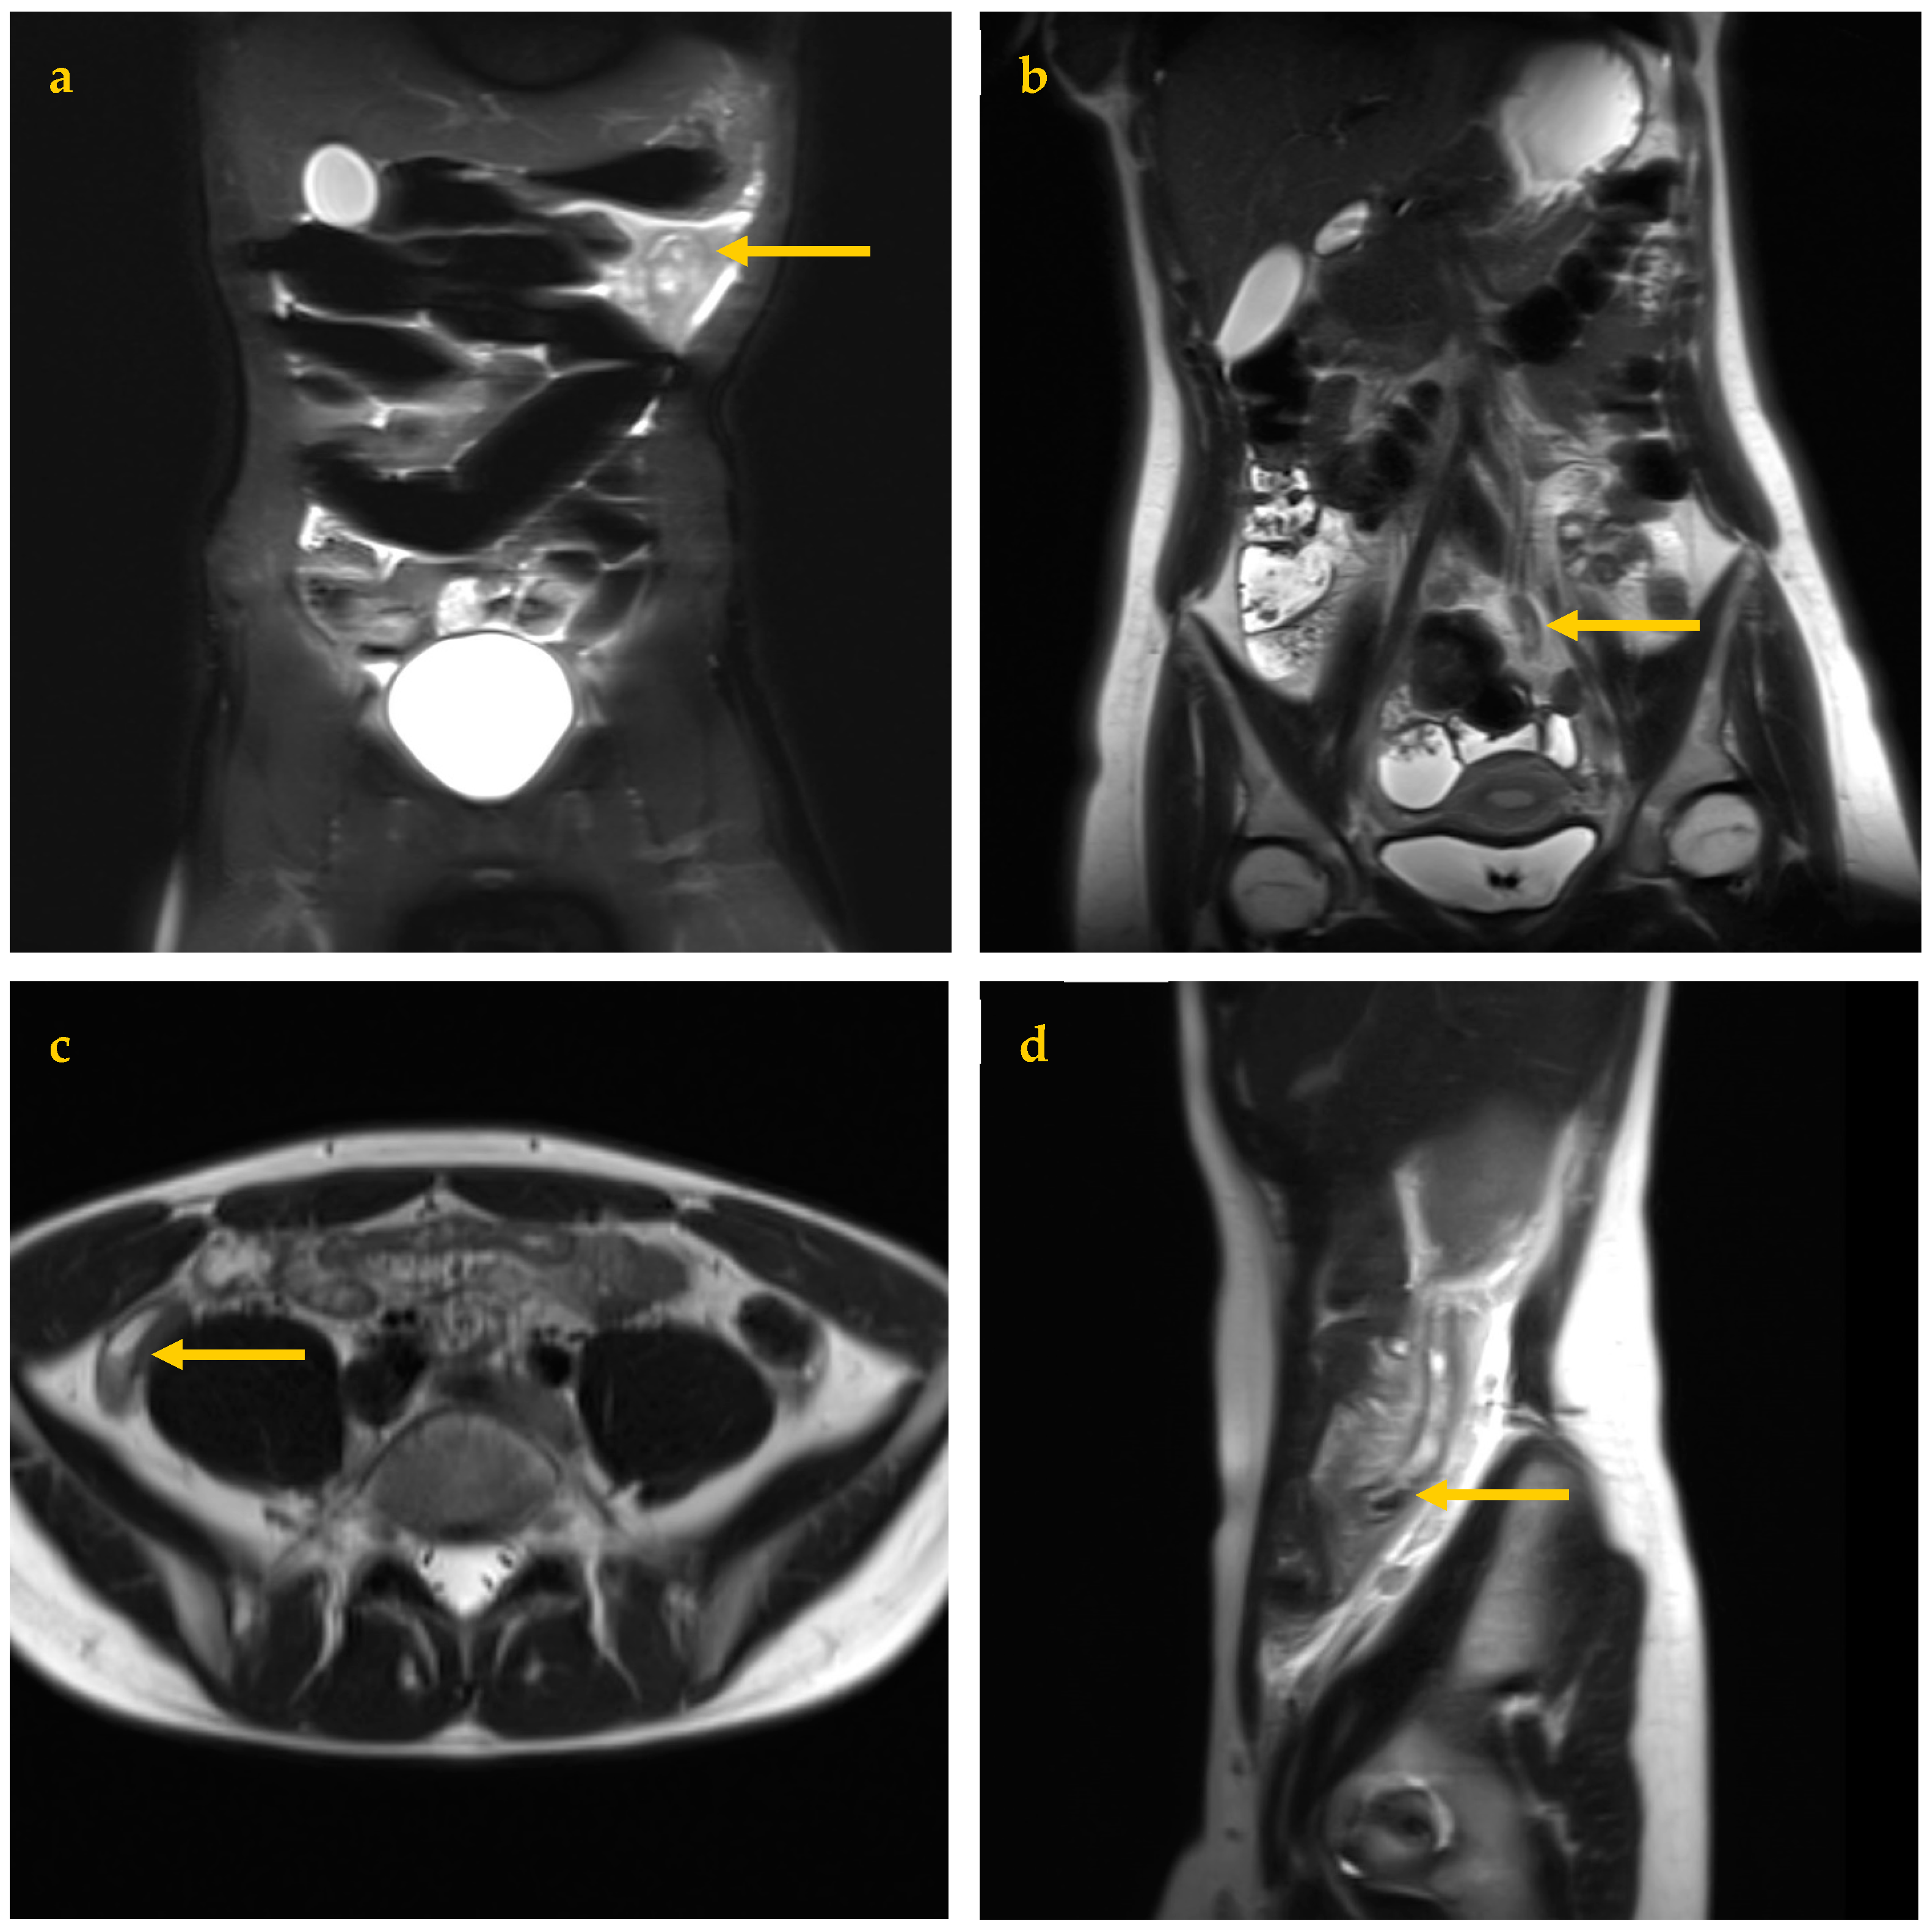

Coronal fast-acquisition (breath-hold) T2 image sets were obtained with and without fat suppression using TR 1500, TE 100, 3 mm thickness, no slice gap, and coverage from the pelvis to top of kidneys, angled along psoas muscles for best kidney coverage. Axial breath-hold T2 images were obtained through the lower abdomen and pelvis with TR 1500, TE 95, 5 mm thickness, and no slice gap. Sagittal breath-hold T2 images were obtained across the right side only with TR 1500, TE 100, 4 mm thickness, and no slice gap, extending from the pelvis to the top of the kidney (Figure 1). Total imaging time for all four sequences was 12 min. Fat-suppressed images can be identified by noting a dark subcutaneous fat appearance. Axial images are sometimes extended to the upper abdomen if symptoms extend to this level.

Optimal imaging was achieved with repeated small inspiratory breath holds. For young children or patients with reduced MRI tolerance, continued gentle breathing was allowed. This would cause mild image blurring but remained adequate for appendix assessment (Figure 1a).

In July 2021, a 19-year-old female was referred with peritonitic abdomen. MRI was the first investigation, and was reported normal. Due to ongoing symptoms, same-day CT was performed, reporting early AA, confirmed at surgery. In retrospect, an inflamed appendix was readily evident at the left (rather than right) iliac fossa, as shown in Figure 1b (reader perception error).

Figure 1. The four MRI sequences used, each demonstrating a different example of proven AA (arrows). (a) Coronal Fat Saturation T2 image, mildly degraded by breathing movement in a 12-year-old male showing bright edema signal due to proven left upper quadrant AA. (b) Coronal T2 image of a 19-year-old female showing a mildly thickened distal appendix extending to the left lower quadrant. (c) Axial T2 image of an 18-year-old male showing typical right lower quadrant AA, including fluid and debris layering within the appendix lumen. (d) Sagittal T2 image of a 14-year-old female showing an inflamed appendix along the right flank with a luminal appendicolith (arrow).